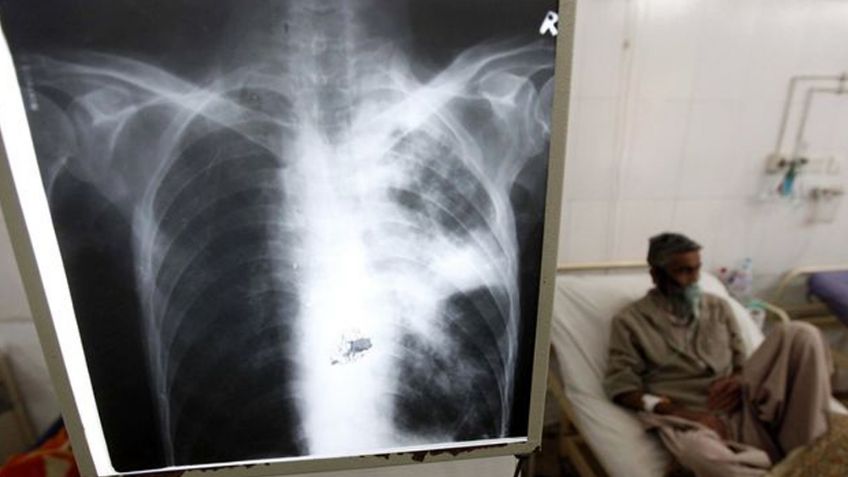

Reino Unido - A pesar de que recientemente se descubrió que el Covid-19 afecta todos los órganos, los pulmones continúan siendo los que más daños presentan después de recuperarse de la enfermedad, pues un reciente estudio concluyó que el 30 por ciento de los pacientes presentan secuelas un año después.

De acuerdo con una reciente investigación de la Universidad de Southampton, hasta un tercio de las personas que fueron hospitalizadas por el virus tiene daños pulmonares un año después de haber superado la enfermedad.

Según los análisis de los expertos estos efectos duraderos se deben por la neumonía causada gracias a la presencia del virus, y suele presentarse de forma mucho más grave en mujeres e incluso sospechan que estos daños pueden durar hasta más de 12 meses.

Para poder llegar a estos resultados, los investigadores dieron seguimiento a 83 pacientes de coronavirus después de que fueron dadas de alta y la mayoría de los voluntarios tuvieron mejorías en los efectos duraderos, pero el 30 por ciento tuvieron un funcionamiento pulmonar reducido.